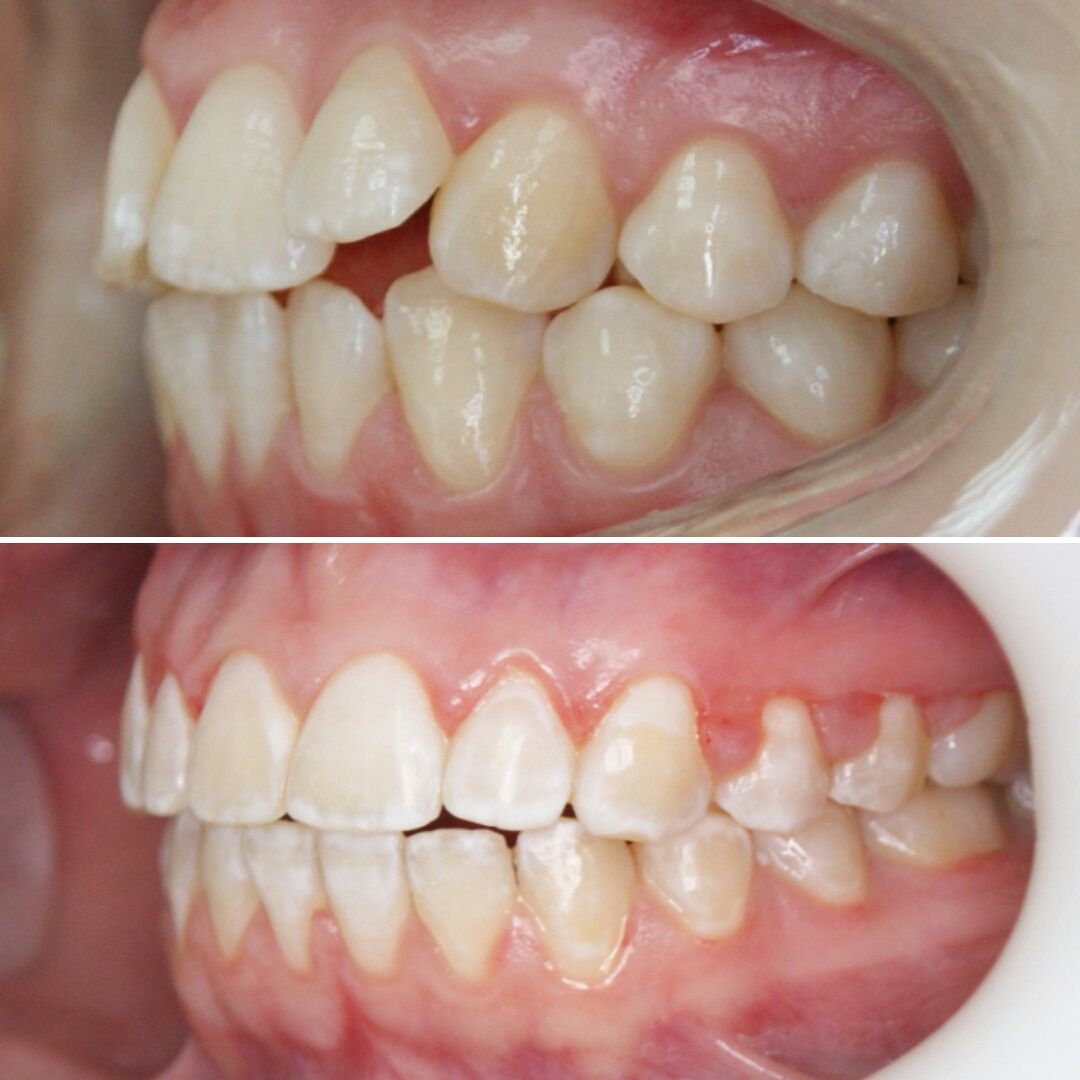

✔Хочу показать жизнь без прикрас ✔Отсутствие должной гигиены во время лечения, которое привело к гингивиту (воспаление десен) и начальной стадии кариеса (меловидные пятна на эмали зубов) ☑Этим постом хочу призвать всех брекетоносцев собдюдать правила гигиены ‼Запомните❗Брекеты не портят зубы! ❗Портит зубы отсуствие тщательной регулярной чистки зубов❗ ✅Дайте своему врачу возможность и время сделать вашу улыбку идеальной

Клинический случай закончен отлично, а вот НЕСОБЛЮДЕНИЕ ГИГИЕНЫ во время ортодонтического лечения привело к изменению эмали зубов!

❗Будьте ответственны к своему здоровью! Соблюдайте гигиену полости рта!❗